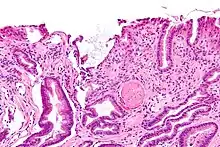

| Endoscopic image of gastric antral vascular ectasia seen as a radial pattern around the pylorus before (top) and after (bottom) treatment with argon plasma coagulation | |

GAVE is characterized by dilated capillaries in the lamina propria with fibrin thrombi. The main histomorphologic differential diagnosis is portal hypertension, which is often apparent from clinical findings.